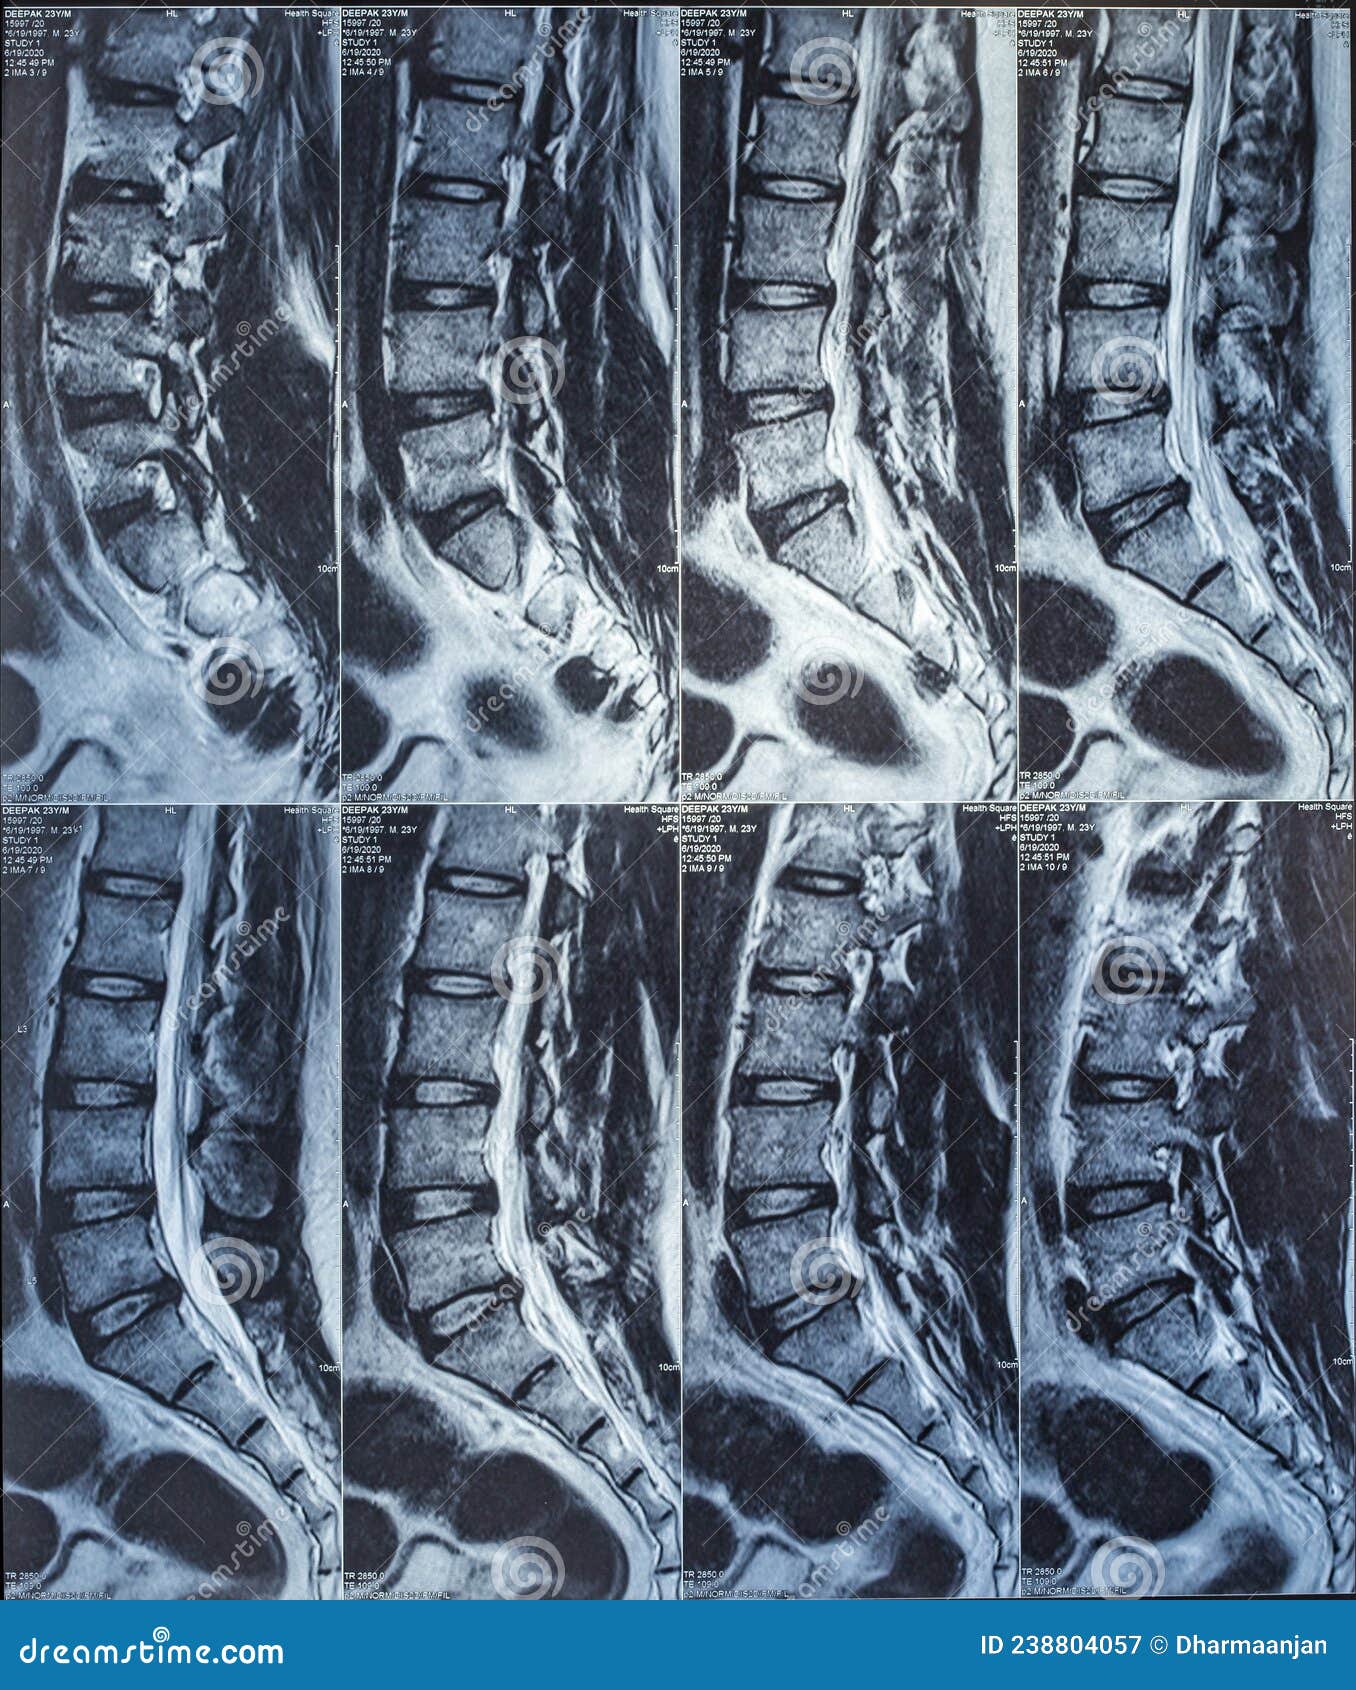

Magnetic Resonance Imaging or Mri Scan Report of Spinal Cord or Lumbar …

Sagittal MRI of herniated L5-S1 lumbar disc. #LowerBackPain | Bulging …

Why You Can’t Just Trust an MRI to Diagnose a Disc Problem! – Hometown …

MRI of a Lumbar-Disk Herniation – License, download or print for £9.92 …

Herniated Disc Mri L5 S1 – Lumbar Herniated Disc – A More in Depth Look …

Lumbar Spine Bulging Disc Vs Herniated Disc Mri / Bulging Disc Vs …

Pre-operative lumbar MRI showing a right paracentral disc herniation at …

Medical Endeavors w/ my Herniated and Degenerative Lumbar Disc: MRI …